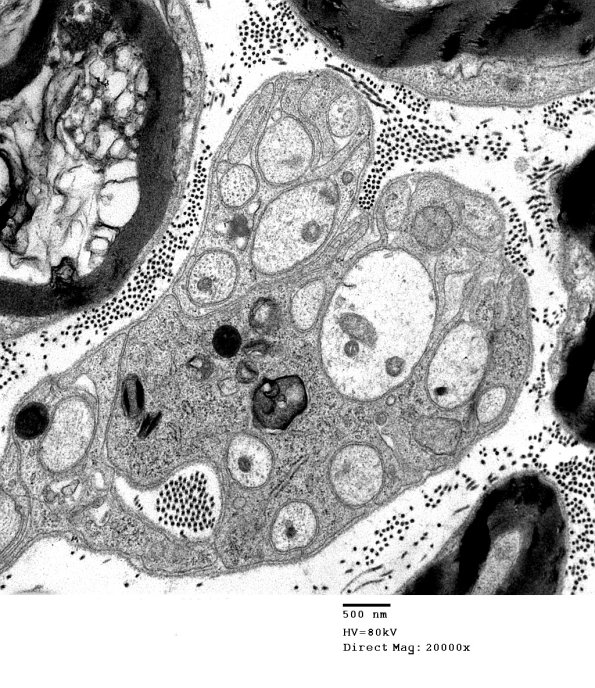

In this Remak bundle axons range in appearance from swelling and pallor to dense aggregates in which it is difficult to identify substructure.